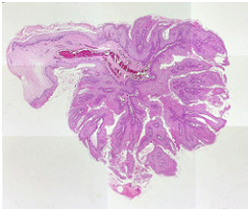

Figure 2 Oral Squamous Papilloma with papillary projections

Figure 3 Papillomas with a fibro-vascular core.

Figure 4 Papillomatous lesions with a prominent fibro-vascular core.

25. Image 3 Courtesy: Pathology Outlines.

26. Image 4 Courtesy: MRCO phth.com.